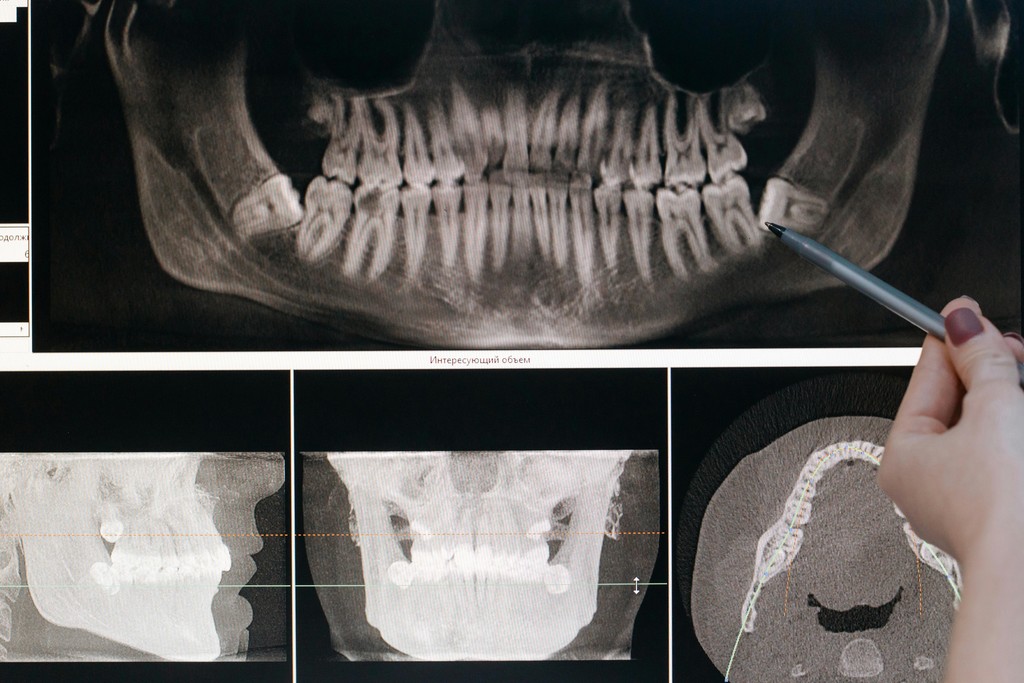

The pre-operative planning model in this case shows the distractor device — a precision instrument that would guide the new bone in the correct vector over the weeks of distraction. The post-distraction OPG shows the distractor in place with the lengthened mandible — new bone visible in the distraction gap.